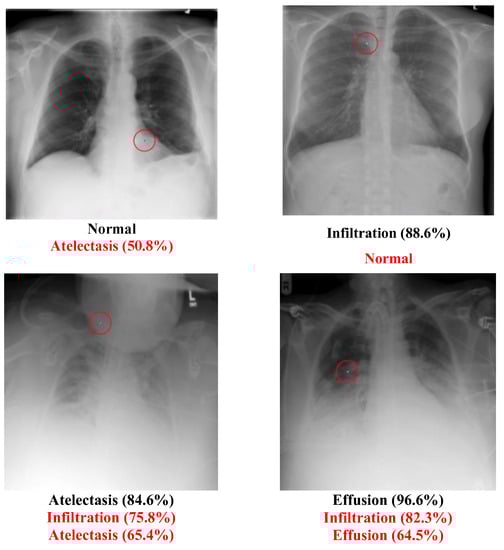

• Example of successfully attacked images

Because 100 experiments will be conducted on each class in each dataset, and there will be a large number of successful images if the success rate is high, only one successful image will be presented for each class. The successfully modified image will be shown with a red circle to indicate the modified pixel. There will be two description lines under each image: a bold black line to indicate the original class and a bold red line to show the class that has been transformed. The number in parentheses shows the confidence level of that class. Notably, there will be some confidence levels that indicate “~100%”. This represents a confidence level above 99.94% because the number will be rounded to one decimal point.

5.2. Multi-Label Dataset

The Chest dataset is a multi-label dataset. Some successful attack examples are shown in Figure 8. The class “Normal” has no confidence level because it means that all labels’ confidence level is below 50%. Figure 9 illustrates some images transformed from a diseased class to a normal class.

It is evident that the “Normal” type had the highest success rate, which is shown in Table 15. The details of the conversion are shown in Table 16. Figure 10 shows the number of diseases in the transformed class of the Chest dataset. The top three were “Infiltration”, “Atelectasis”, and “Effusion”. Table 9 shows that it is easier to transform diseased images into normal ones.